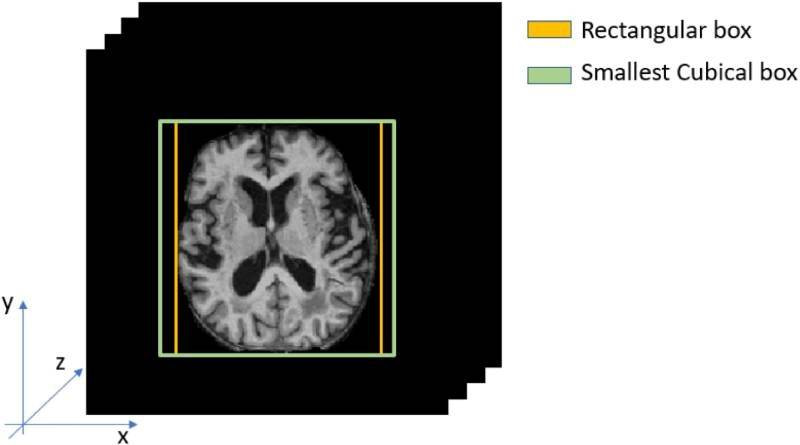

A continuación, diseñaron e implementaron una solución completamente basada en redes neuronales convolucionales 3D que extraía características de todo el volumen cerebral en tres dimensiones. Una vez hecho esto, aplicaron una estrategia de entrenamiento capaz de manejar un conjunto de datos altamente desequilibrado e incompleto.

Extracción de la región cerebral de cada paciente. / UPM